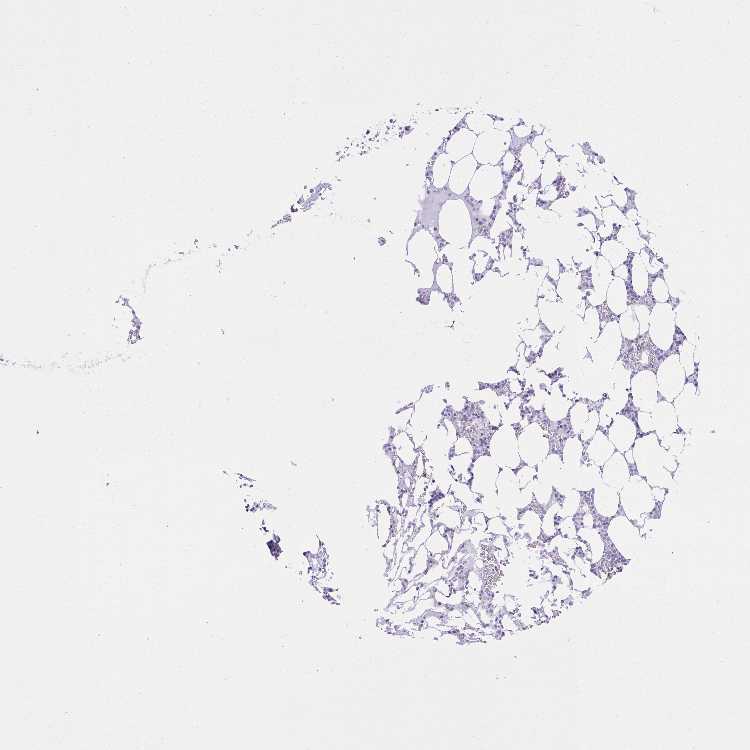

TISSUE PRIMARY DATA BONE MARROW Show tissue menu

BONE MARROW - Antibody stainingi

Antibody staining in the annotated cell types in the current human tissue is reported as not detected, low, medium, or high, based on conventional immunohistochemistry profiling in selected tissues. This score is based on the combination of the staining intensity and fraction of stained cells.

Each image is clickable and will lead to virtual microscopy that enables deeper exploration of all samples and also displays staining intensity scores, fraction scores and subcellular localization as well as patient and tissue information for each sample.

Antibody HPA055868

Hematopoietic cells Not detected